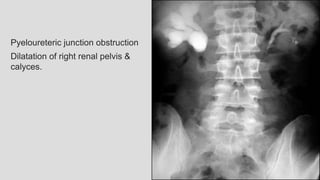

Pyeloureteric junction obstruction

Dilatation of right renal pelvis &

calyces.